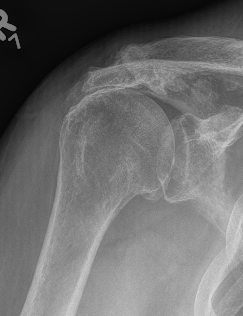

Differential diagnosis

Glenohumeral osteoarthritis

- no superior migration of humeral head

- beard osteophytes on inferior aspect of the humeral head